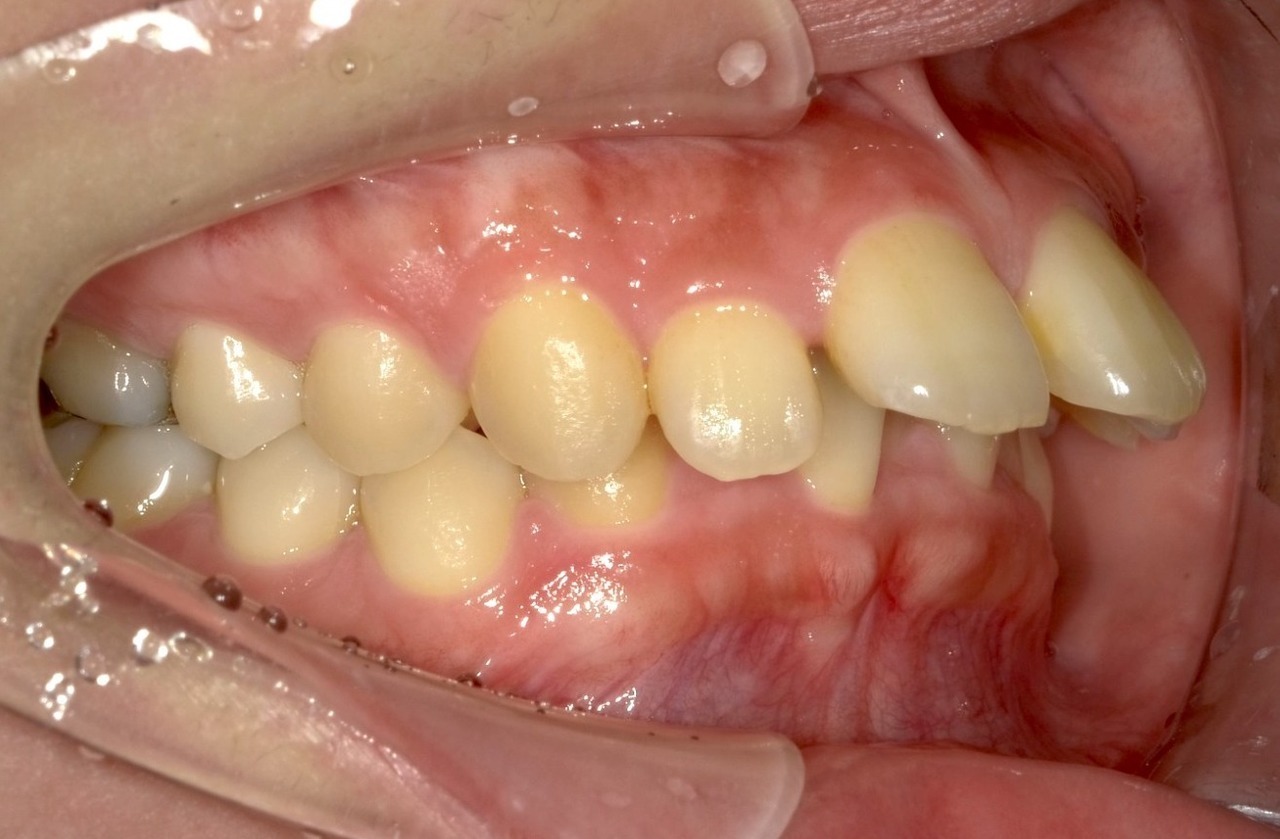

マウスピース矯正の失敗例

歯を並べるスペースの確保のために歯を削りすぎた結果、歯並びが完全に治らず前歯がすきっ歯になっています。

奥歯の上下が噛み合わなくなっています。これではお食事をとるのにも不自由します。

当院には、他院でマウスピース矯正を受けたものの、思うような結果が得られなかった患者さまが数多く来院されます。

この患者さまはインビザラインを4年間続けたものの、不十分な診断と治療計画によって歯を削りすぎてしまい、歯並びも咬み合わせも整わなかったケースです。